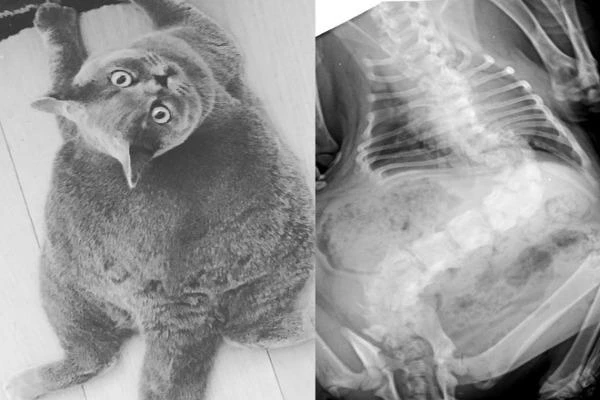

Gương mặt lúc nào cũng ngơ ngác, thân hình mũm mĩm, tròn như quả bóng là nhận xét chung của nhiều người khi nhìn thấy loạt ảnh về chú mèo tên Pitoe (4 tuổi). Bên cạnh nhiều bình luận khen đáng yêu, không ít người bày tỏ sự lo ngại cho sức khỏe Pitoe, sợ chú bị béo phì do ăn uống quá độ. Tuy nhiên, một trong những lý do khiến Pitoe có vẻ ngoài như vậy là căn bệnh vẹo cột sống hiếm gặp ở mèo.

Chú mèo 4 tuổi thuộc giống mèo Anh lông ngắn được gia đình của Marie nhận nuôi cách đây không lâu. "Vì Pitoe bị vẹo cột sống khá nghiêm trọng nên cơ thể của nó ngắn hơn nhiều so với những con mèo bình thường. Bố mẹ tôi là bác sĩ thú y. Một ngày nọ, họ phát hiện Pitoe sắp bị một người bán mèo bỏ rơi vì vẻ ngoài xấu nên quyết định nhận nuôi", Marie nói với Bored Panda.

"Nhiều người lo lắng Pitoe bị béo phì nhưng thực ra thân hình nó như vậy một phần do cột sống bị vẹo. Chúng tôi vẫn luôn cho nó kiểm tra sức khỏe thường xuyên và đảm bảo chế độ ăn lành mạnh. Nó cũng không gặp đau đớn gì", Marie cho biết.